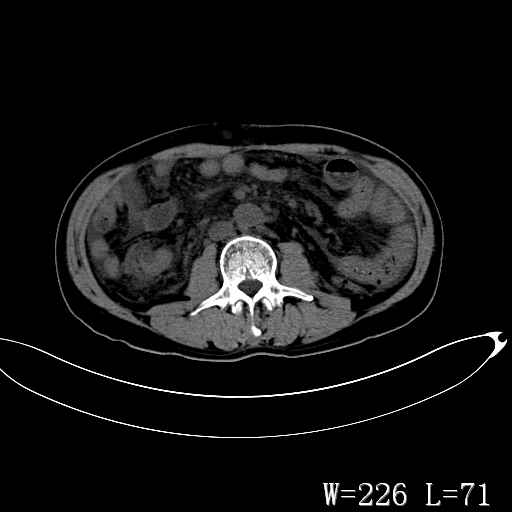

男,52岁,门脉高压断流术后1年,发现腹部肿物2月。

1)前腹壁中线区(脐上方)囊性占位性病变,考虑淋巴囊肿。2)腹水。